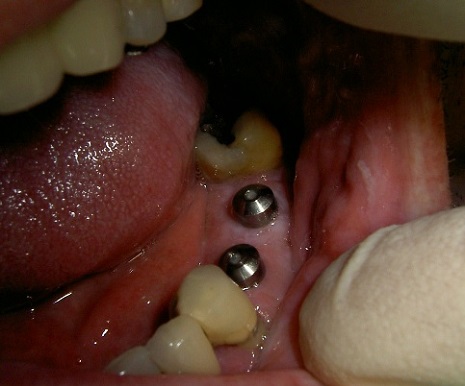

Ejemplo Implantes